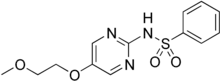

Glymidine sodium

| Formula | C13H15N3O4S |

| Molar mass | 309.34 g·mol−1 |

SMILES

Glymidine sodium (INN, also known as glycodiazine; trade name Gondafon) is a sulfonamide antidiabetic drug, structurally related to the sulfonylureas. It was first reported in 1964, and introduced to clinical use in Europe in the mid to late 1960s.[1]